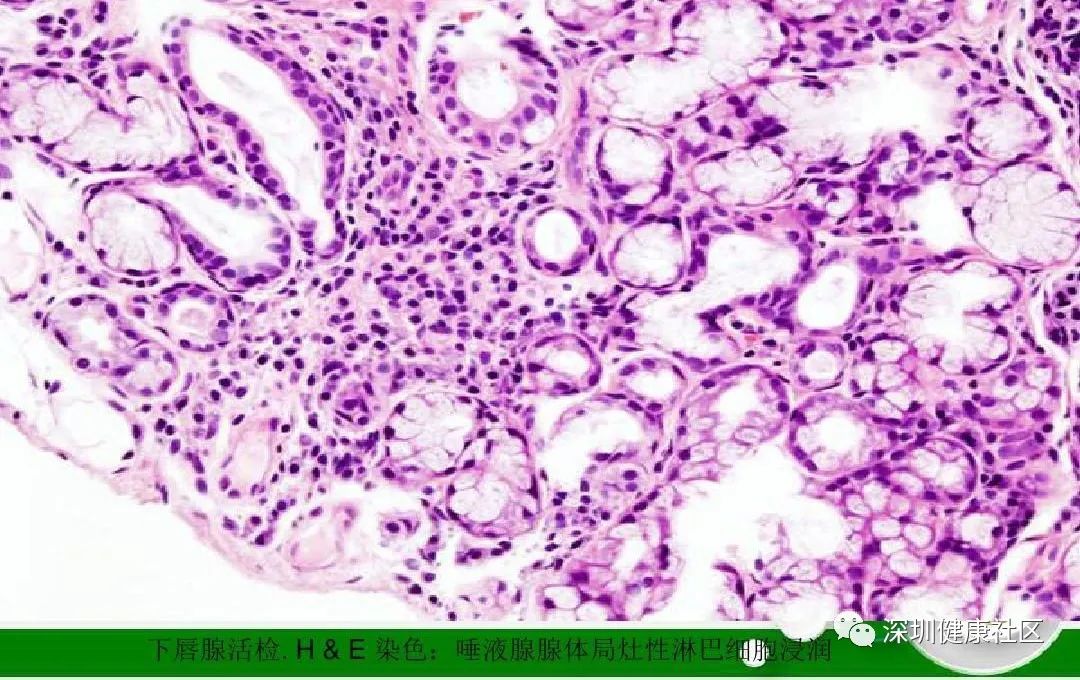

此外,抗α-胞衬蛋白抗体还可对SS炎性活动状况的作出评估,其抗体滴度常与唾液腺淋巴细胞浸润程度密切相关。